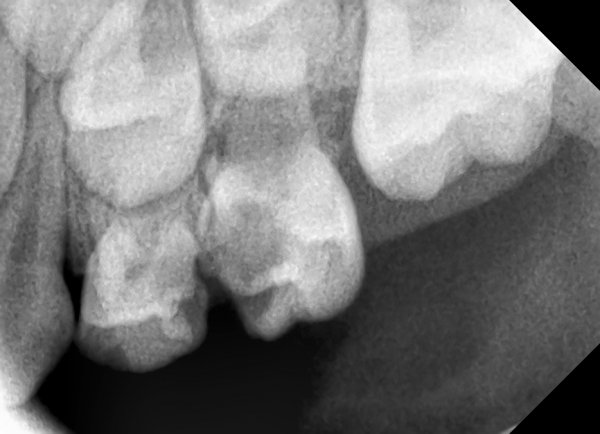

Доброе утро! Мне делали снимок в 14 лет, сказали у меня молочные зубы еще 2. Сказали сами выпадут. Сейчас мне уже почти 19. Один только шатается, болит жуть как. И над ним шишечка на десне, белая немного. Мне его нужно выдирать или сам выпадет? И еще я проживаю м.Петровско-Разумовская, Дмитровское шоссе 43-1. Мне если что в вашу поликлинику идти? Просто с детской, я так ни разу и не ходила к стоматологу.

Шишечка - это воспаление, зуб необходимо удалить.